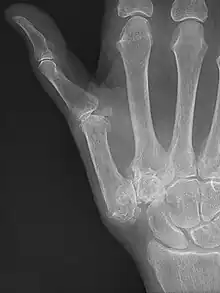

Diagnosis

TMC OA is diagnosed based on symptoms and signs.[8] Radiographs can confirm the diagnosis and the severity of TMC OA. Other diagnoses in this region include scaphotrapezial trapezoid arthritis and first dorsal compartment tendinopathy (De Quervain syndrome) although these are usually easy to distinguish.

Classification

TMC OA severity was classified by Eaton and Littler which can be simplified as follows:[21][22]

Stage 1:

Stage 2:

Stage 3:

Stage 4:

A simpler classification is no arthritis, some arthritis, and severe arthritis.[23] This simpler classification system omits the potentially contradictory details of the Eaton/Littler classification and keeps scaphotrapezial arthrosis separate.